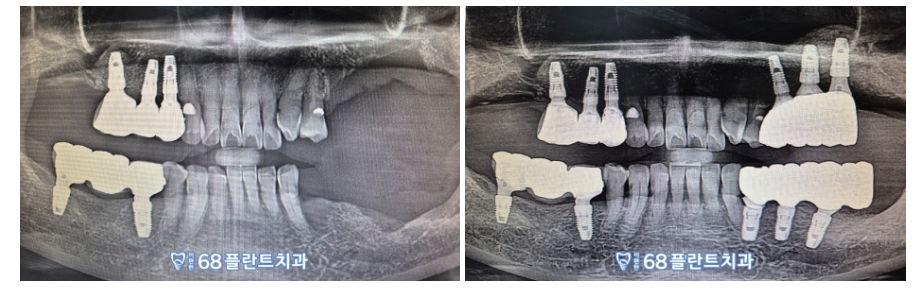

◆ 전 > 후 ◆

​(2023.01.23ㅡ>2023.8.14)

임플란트를 심고

치아 뿌리 역할을 하는 픽스처가

충분히 뼈에 잘 유착될 수 있도록

충분히 기다린 후,

치아의 머리 역할을 하는

크라운(보철물)을 올려

치료를 마무리 했습니다.

환.자분께서 이제 왼쪽으로도

편안하게 식사할 수 있겠다며

만.족해 하셨고,

너무 편안하게 잘 받았다며

감사의 인사를 전해주셨답니다!